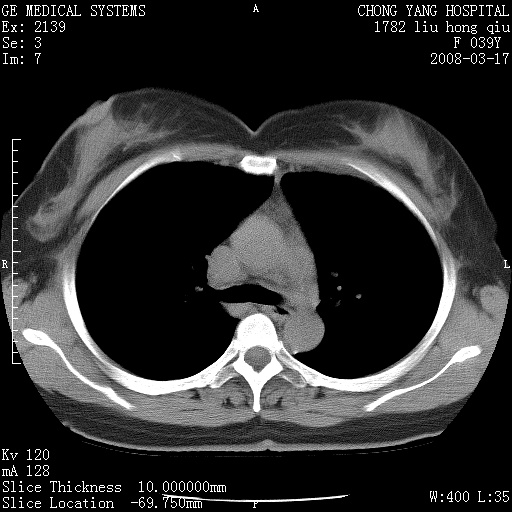

以下是引用yangxue121在2008-5-31 20:24:00的发言:[br]考虑多发胸膜间皮瘤[br]左侧少量胸腔积液[br]肝脏密度不均

以下是引用王仕学在2008-5-31 20:10:00的发言:[br]考虑胸膜间皮瘤。

以下是引用长城干红在2008-5-31 21:42:00的发言:[br]肝脏密度不均,建议增强扫描,胸膜下多发结节,考虑为胸膜来源的原发肿瘤或转移瘤。